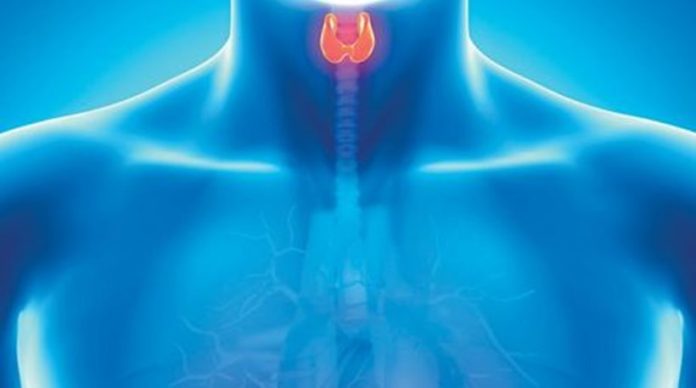

Με τη συμμετοχή κορυφαίων χειρουργών θυρεοειδούς πραγματοποιήθηκε πρόσφατα στην Ακαδημία Ιατρικών Ερευνών της Σιγκαπούρης το 2o Διαστοματικό Εργαστήριο Θυρεοειδεκτομής, στο οποίο κύριο θέμα ήταν η εκπαίδευση επιστημόνων απ’ όλο τον κόσμο στη νέα επαναστατική τεχνική αφαίρεσης θυρεοειδούς από το στόμα. Μοναδική ελληνική παρουσία ήταν του Εξειδικευμένου Χειρουργού Ενδοκρινών Αδένων Ευάγγελου Καρβούνη, Διδάκτορος του Πανεπιστημίου Αθηνών και Διευθυντή του Κέντρου Αριστείας της Χειρουργικής Θυρεοειδούς και Παραθυρεοειδών Αδένων, στην Ευρωκλινική Αθηνών, ο οποίος και εκπαιδεύτηκε στη συγκεκριμένη μέθοδο.

Η συγκεκριμένη πρωτοποριακή χειρουργική τεχνική αφαίρεσης θυρεοειδούς μέσω φυσικών οπών του σώματος, εφαρμόζεται ήδη επιτυχώς σε κάποιες χώρες του εξωτερικού, και περιλαμβάνει επέμβαση μέσω του στόματος του ασθενούς, χωρίς τομή στο λαιμό, χωρίς σημάδια και με μηδενική αισθητική αλλοίωση.

Σχολιάζοντας την εμπειρία της εκπαίδευσης ο Δρ. Καρβούνης επισημαίνει πως «Αντιμετώπισα με πρωτόγνωρο επιστημονικό δέος τη νέα αυτή τεχνική αφαίρεσης θυρεοειδούς από το στόμα, έχοντας την τύχη να εκπαιδευτώ στην ανωτέρω μέθοδο, από τον κορυφαίο στον κόσμο, Ταϊλανδό χειρουργό Dr Angkoon Anuwong, ο οποίος στη διάρκεια της εντατικής εκπαίδευσης, μας ανέλυσε ενδελεχώς τα οφέλη και τις ιδιαιτερότητες της καινοτόμου αυτής τεχνικής».

«Η θυρεοειδεκτομή από το στόμα» συμπληρώνει ο Δρ. Καρβούνης, «που μέχρι πρότινος έμοιαζε επιστημονική φαντασία, δείχνει να αλλάζει την ιστορία της χειρουργικής θυρεοειδούς στον κόσμο και αυτό είναι ένα ιδιαίτερα ελπιδοφόρο μήνυμα, που ελπίζω πολύ σύντομα να ενταχθεί στη φαρέτρα μας και στην Ελλάδα προκειμένου να αντιμετωπίσουμε, με τη μικρότερη δυνατή παρέμβαση στο σώμα του ασθενούς, τις παθήσεις του θυρεοειδούς».

Αξίζει να σημειωθεί πως η διαστοματική αφαίρεση θυρεοειδούς με χρήση βιντεοκάμερας, είναι μία πρωτοπόρος επέμβαση παγκοσμίως, η οποία θεωρείται πολλά υποσχόμενη για το εγγύς μέλλον, δεδομένου ότι επί του παρόντος μόνο εξειδικευμένα κέντρα, με μεγάλο αριθμό περιστατικών ενδοκρινικής χειρουργικής και υπό συγκεκριμένες προϋποθέσεις και κριτήρια, φαίνεται να μπορούν να αναπτύξουν την ιδιαίτερη αυτή χειρουργική προσέγγιση.